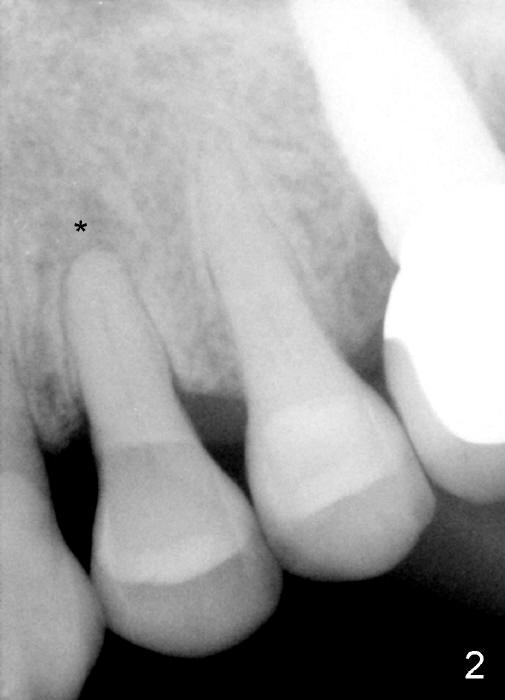

A 72-year-old lady has a deep cervical defect of the tooth #12 (Fig.1 ^) associated with buccal apical fistula (*) and periapical radiolucency (Fig.2 *). To prevent bleach leakage during root canal therapy (RCT), composite is used to repair the defect (Fig.3 (CT coronal section) C) prior to access. The buccal canal is not located probably due its own or iatrogenic (due to composite) obliteration. After thorough debridement of the lingual canal, Calcium Hydroxide paste is placed (*).